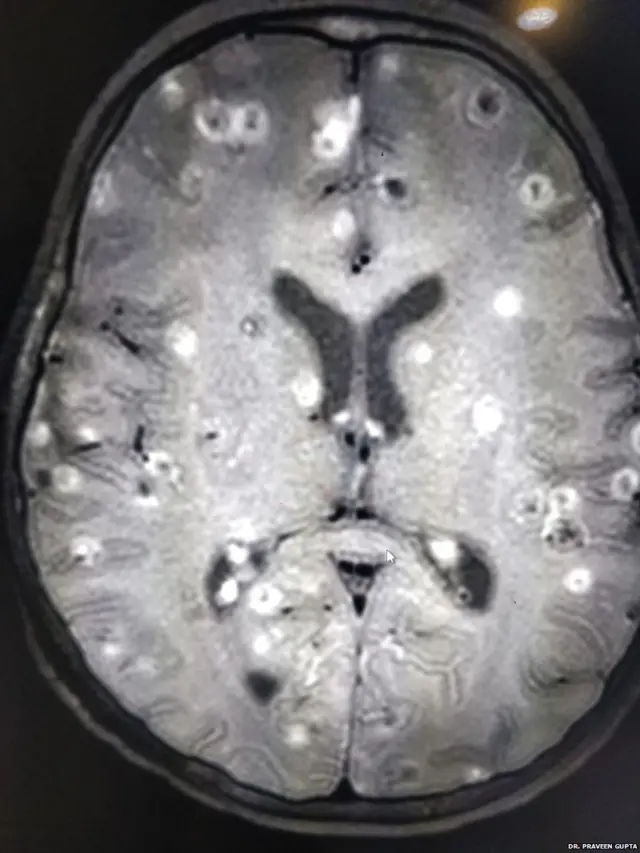

بچی کے دماغ میں سو سے زیادہ ٹیپ ورم کے انڈے تھے جو سکین ہونے پر دماغ میں خون کے لوتھڑوں کی صورت میں نظر آ رہے تھے۔

ڈاکٹر گپتا نے بتایا کہ ’جس وقت بچی ہسپتال لائی گئی وہ ہوش میں نہیں تھی۔ سکین میں اس کے دماغ میں صفید رنگ کے دھبے نظر آ رہے تھے۔ یہ دھبے کیڑے کے انڈے تھے۔ وہ بھی ایک یا دو نہیں، سو سے زیادہ انڈے۔‘